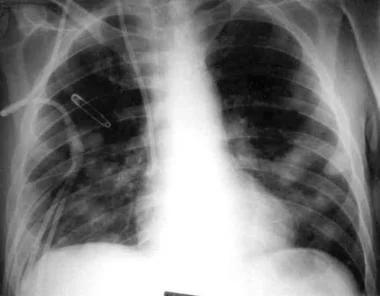

可能会观察到斑片状浸润,结节(见图1),实变,空洞或胸腔积液。

纵隔淋巴结肿大在地方性真菌肺炎患者中很常见。淋巴结肿大可以是单侧或双侧。感染曲霉菌引起中性粒细胞减少的患者(60%),常见磨玻璃影包围肺结节,称为“晕征” 。

图1 胸部X线片示多发肺结节。因慢性粒细胞白血病进行骨髓移植后,该患者接受皮质类固醇激素治疗。对支气管肺泡灌洗液真菌培养后显示曲霉菌和其他菌种。

CT对免疫力低下非特异性浸润患者的早期诊断具有一定作用。CT扫描可观察曲霉菌患者的晕征。一项研究发现,在235例侵袭性曲霉菌感染的患者中,多达61%的患者出现晕征。